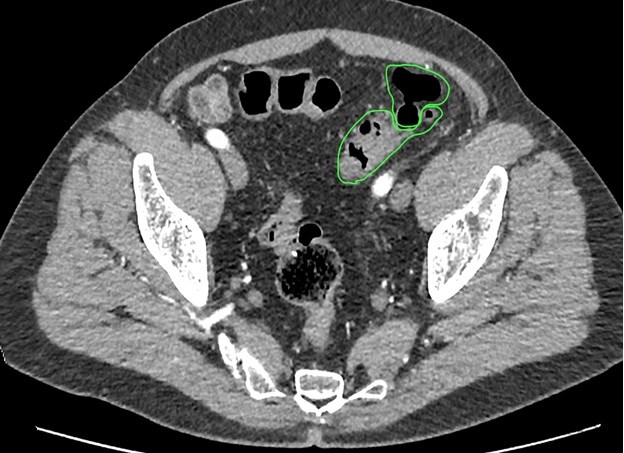

«Золотым стандартом» диагностики дивертикулярной болезни является ирригоскопия. Этот метод позволяет определить количество дивертикулов, их точное местоположение, размеры и форму. Суть процедуры заключается в введении рентгенконтрастного препарата в толстую кишку, после этого выполняется серия рентгенологических снимков, позволяющих оценить состояние толстой кишки. На представленных фотографиях стрелками указаны устья дивертикулов толстой кишки. Синими стрелками мы отметили множественные дивертикулы ободочной кишки. Именно так они выглядят при компьютерной томографии.

Не менее важными методами являются ультразвуковая диагностика и компьютерная томография. Благодаря своей малоинвазивности, простоте выполнения, ультразвуковая диагностика очень актуальна на этапе первичного обследования. Она позволяет увидеть наличие дивертикулов, выявить косвенные признаки их воспаления, такие как инфильтрат, абсцесс или предположить генерализованную форму – перитонит.

Для уточнения данных, полученных при ультразвуковом исследовании, при возникновении сомнений и для уточнения диагноза выполняется спиральная компьютерная томография. Виртуальная компьютерная томография позволяет воссоздать трехмерное изображение толстой кишки, включая пораженные участки. С помощью этой методики можно точно определить границы инфильтрата или абсцесса, другие органы, вовлеченные в воспалительный процесс.

Виртуальная колоноскопия. Устье дивертикула